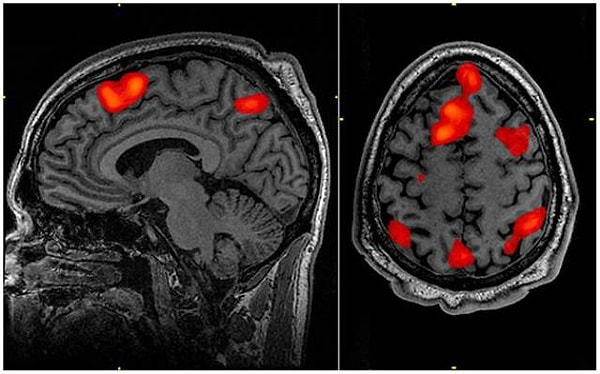

8. Обзор многолетних исследований показывает, что после тестирования электростимуляции височной доли пациенты испытывают ощущение пребывания в нереальности, а также дежавю.